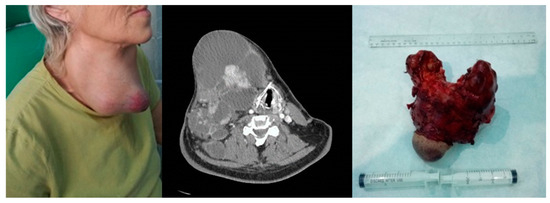

Figure 5. Anaplastic thyroid carcinoma. Left image—clinical aspect. Center image—axial CT scan with tumor displacement of the airway. Right image—resection piece 750 g.

Breakdown by evolution: the LTS giant follicular cyst case was followed at 1 month and 3 months and then endocrinologically discharged, and the five poly nodular goiter follicular adenoma cases were followed at 1 month and 6 months and entered in the endocrinological dispensary. Among the 21 cases of the studied group, there were 16 survivors at 5 years, in oncological monitoring at 3 months. The four cases of anaplastic carcinoma resulted in death, as well as one case of papillary carcinoma with multiple metastatic disease. The outcome was through tracheal invasion—four cases, respectively, through multiple metastatic disease—one case. Among the four cases of anaplastic carcinoma, three cases followed chemotherapy, with resumption of evolution and exitus, respectively, and one case had a resumption of evolution 6 weeks postoperatively, with exitus, Figure 5.

Regarding the distant evolution, 16 (76.19%) of the 21 cases of giant thyroid tumors in patients with multiple comorbidities survived, following a program of oncological monitoring every 3 months. All cases of anaplastic carcinoma resulted in death (four of four) and one case of papillary carcinoma with multiple metastatic disease, confirming data from the literature regarding this type of neoplasia [33].